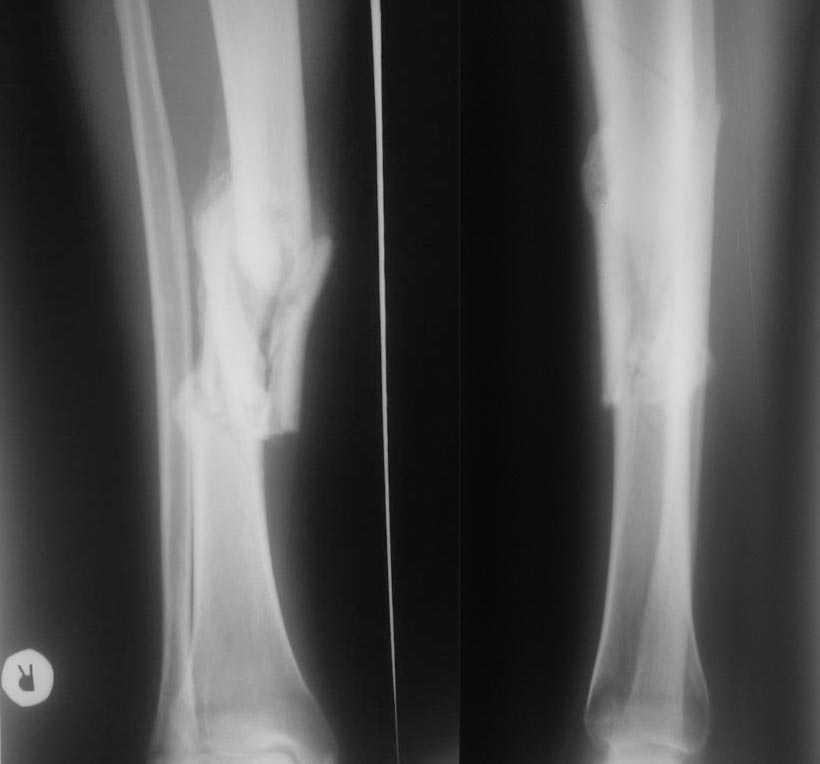

Неправильносросшийся перелом голени. |

Уважаемые коллеги. К нам в клинику. на консультацию обратился больной с неправильносросшимся переломом правой голени.

Травма автодорожная, три месяца назад, перелом голени открытый. Почему именно доктора не занимались переломом голени больной пояснить не может, видимо не позволяло общее состояние и наличие прочих повреждений. На момент осмотра голень в гипсовой лангетной повязке до коленного сустава, кожные покровы чистые, отек незначительный. На р-х выраженная костная мозоль.

Просьба поделится мнениями о тактике лечения.